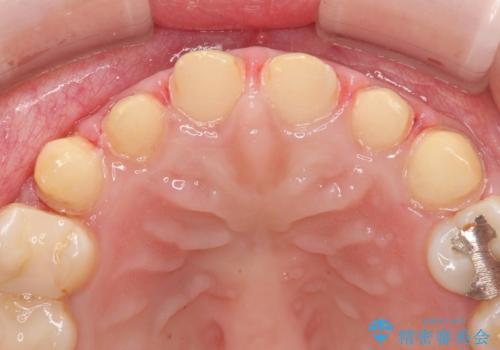

- 前歯の色味が気になるとのことで来院された患者様です。今までに保険のプラスチック(コンポジットレジン)で虫歯の治療をしており経年的な劣化により着色が目立つようになっていました。また歯と歯の隣り合っているところに段差もあり虫歯になっているところもあったため前歯6本のオールセラミッククラウンによる治療を行うこととなりました。

拡大鏡視野下で保険のプラスチック(コンポジットレジン)、虫歯を除去し、オールセラミッククラウンに適した形にしました。

また今回は6本と本数も多かったため個歯トレーを用いて複数本の歯を正確に型どりしています。